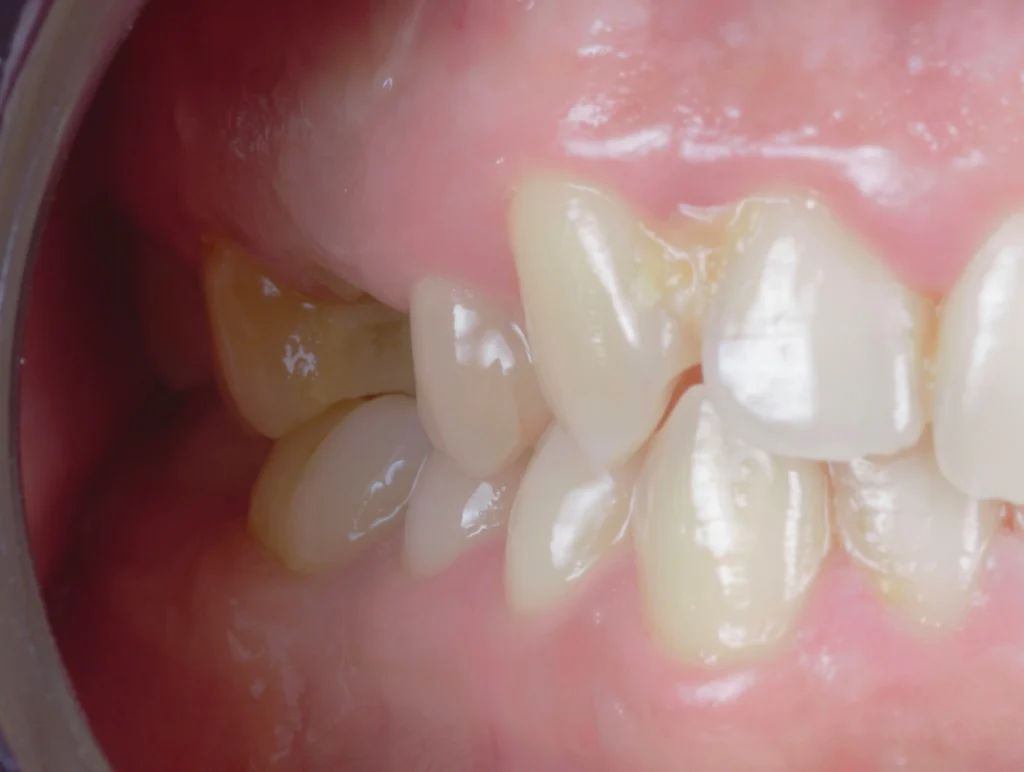

Using a computer-aided surgical guide, we performed a precise extraction and immediately placed the implant in the ideal position. Right after the intervention, the patient was provided with a temporary tooth, maintaining both appearance and comfort during the healing phase.

After a healing period of six months, the implant achieved excellent osseointegration. At this stage, we proceeded with the final restoration phase, ensuring everything was perfectly stable and ready.

We delivered a high-quality, screw-retained zirconia crown that blends seamlessly with the natural teeth. The result is a subtle yet powerful transformation—a small change that made a big difference in the patient’s smile and confidence.Â